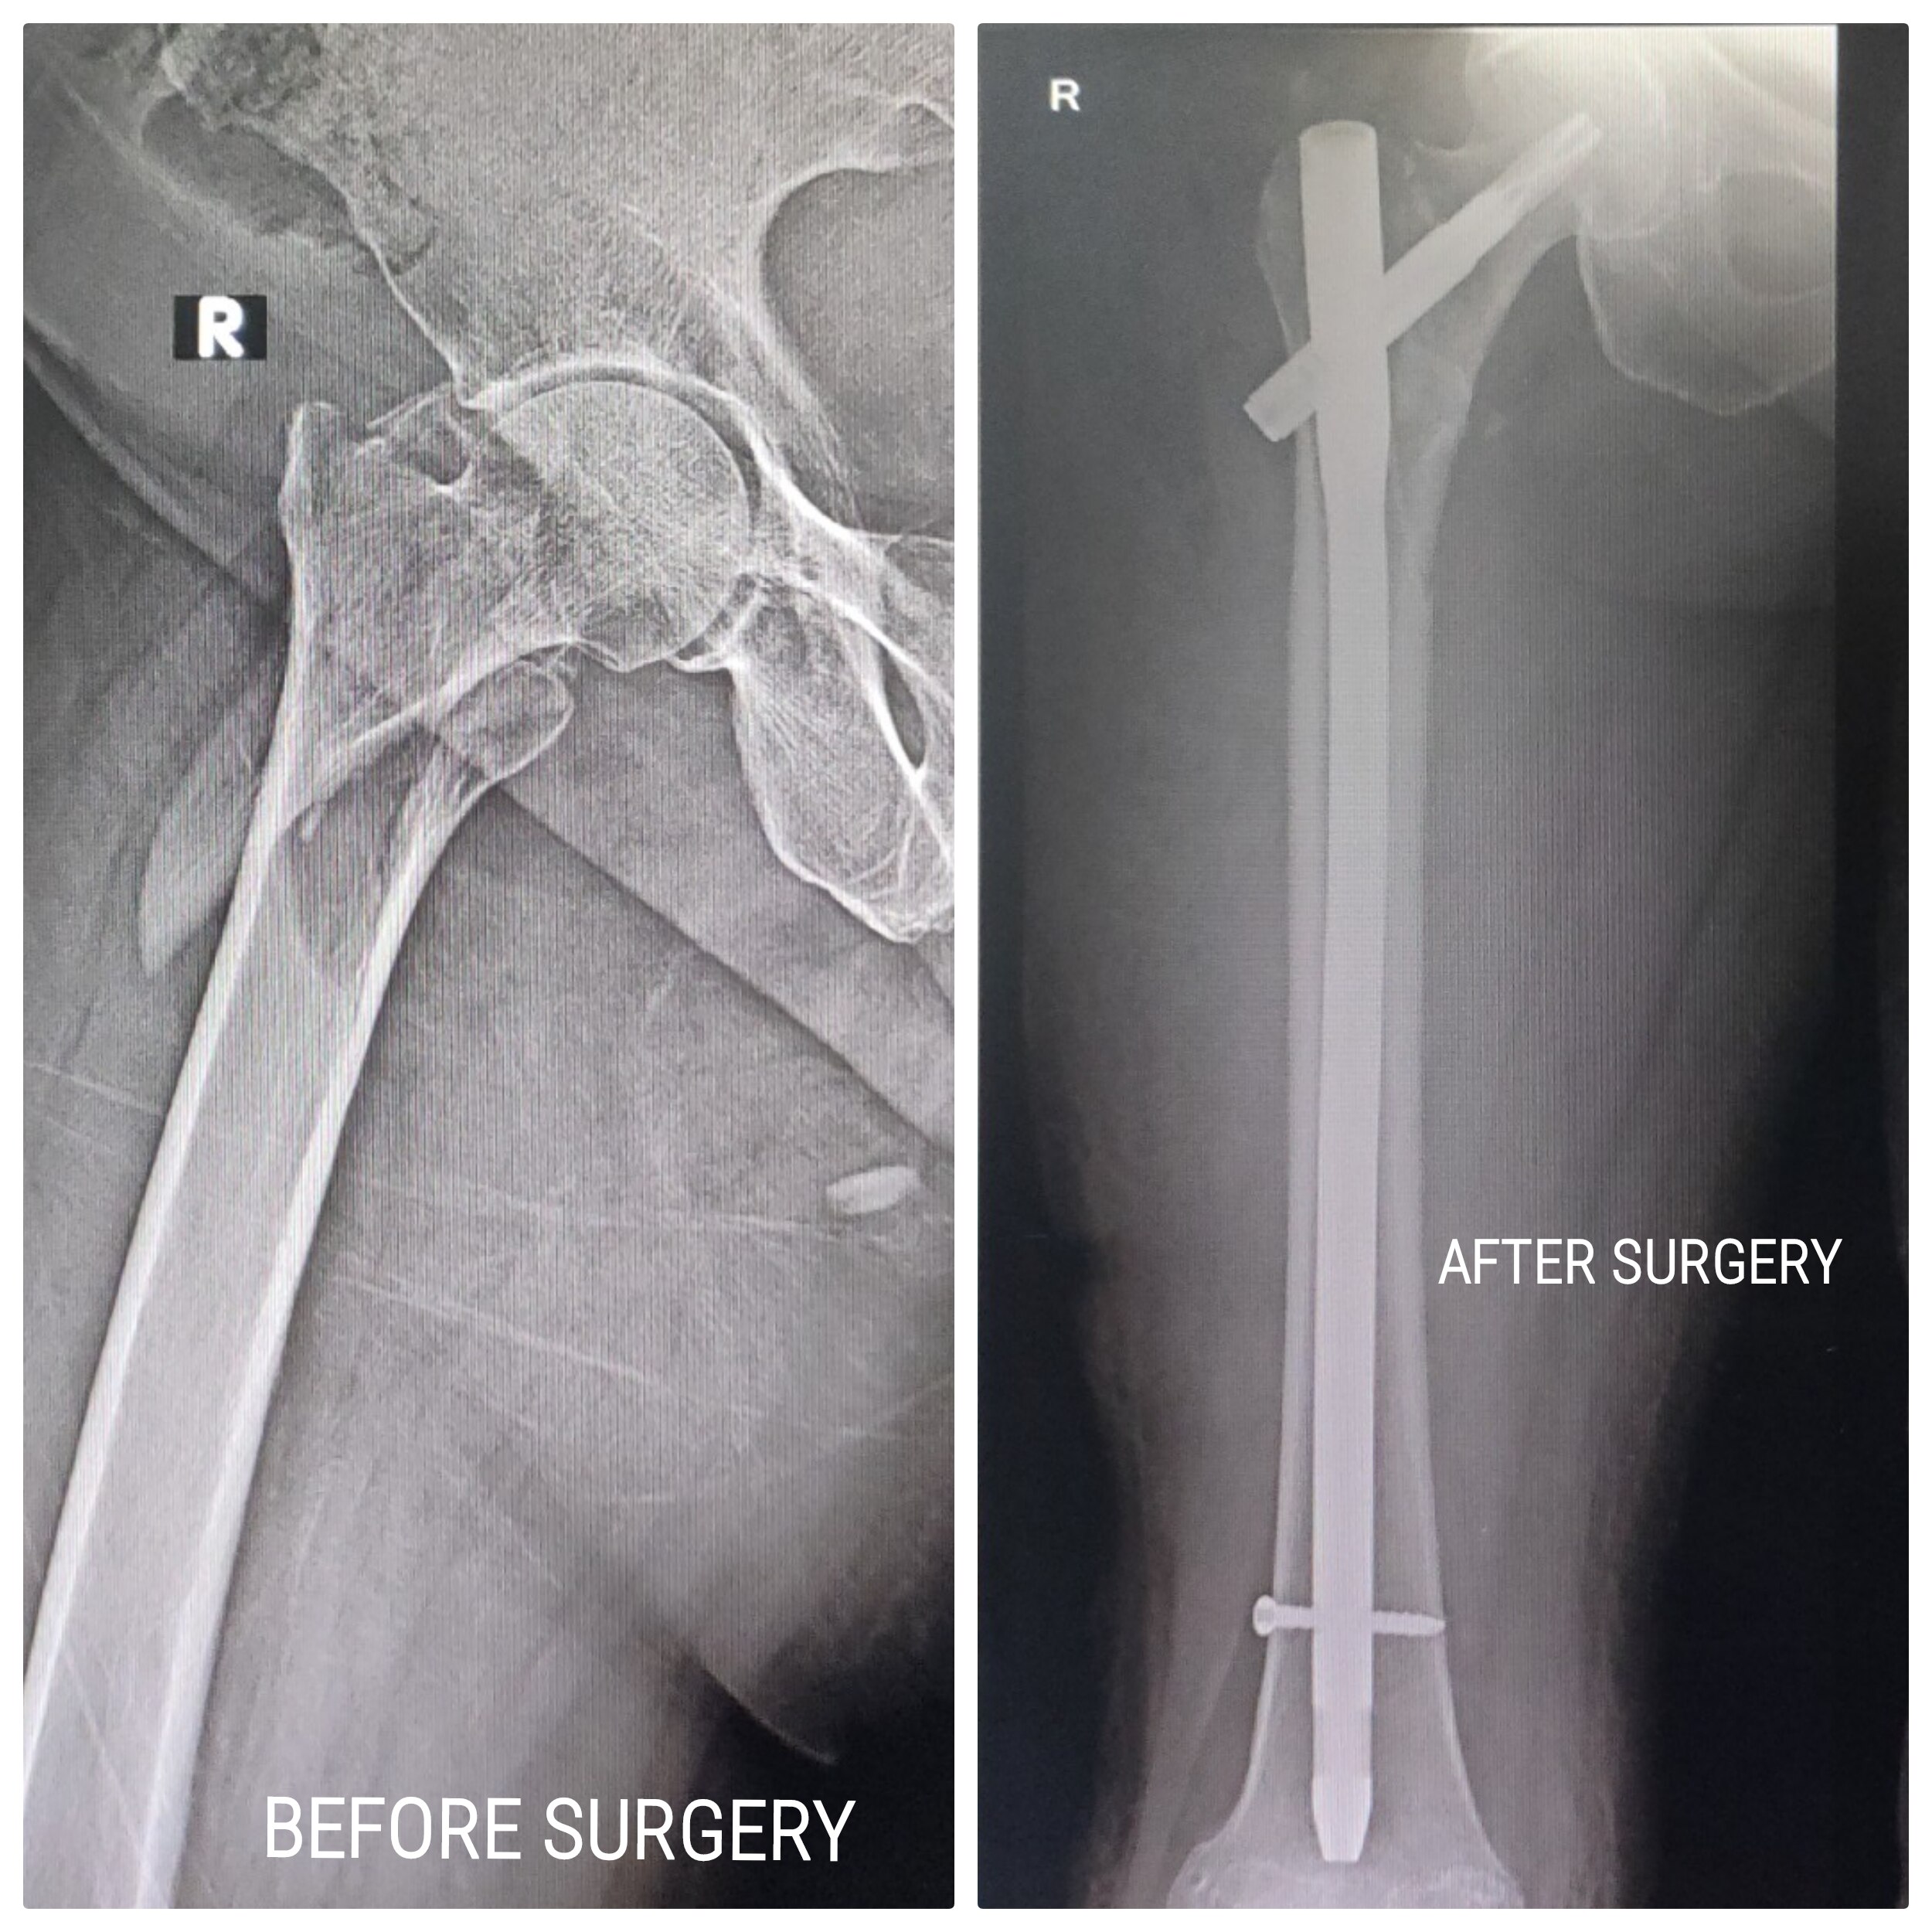

Welcome to the world of orthopedic excellence, where your health and well-being are our utmost priorities. Dr. Chetan Singh , an accomplished orthopedic surgeon, has been a dedicated practitioner in the vibrant city of Bhopal for the past 8 years. His unwavering commitment to providing exceptional orthopedic care has earned him a reputation as a trusted healthcare professional in the region. Meet Dr. Chetan Singh is a highly skilled orthopedic surgeon who has dedicated his career to improving the lives of patients suffering from orthopedic conditions. His educational journey began with the completion of an MBBS degree from Devi Ahilya Vishwa Vidyalaya, Indore, M.P. in 2015, where he laid the strong foundation for his medical expertise. Driven by his passion for orthopedics and a desire to offer the best care possible, Dr.Chetan Singh continued his educational journey. In 2019, he successfully achieved a Master of Surgery (MS) in Orthopedics from Madhya Pradesh Medical Science University, Jabalpur. This rigorous training equipped him with the knowledge, skills, and advanced techniques necessary to diagnose, treat, and manage a wide spectrum of orthopedic conditions.